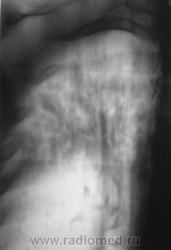

Томограммы.